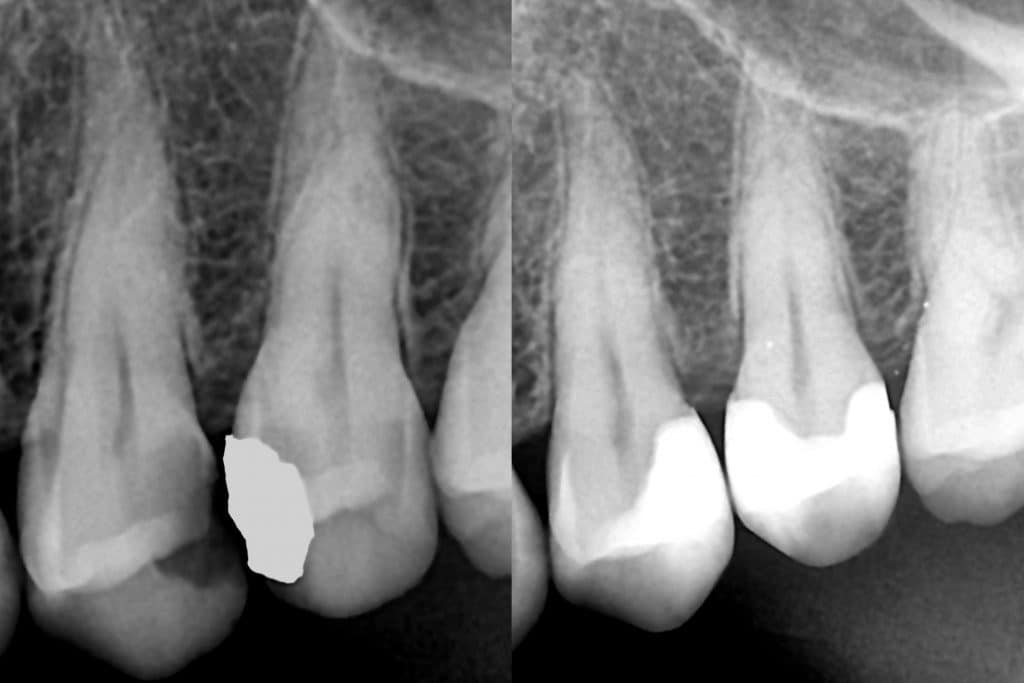

Pre op Vs Post op radiograph